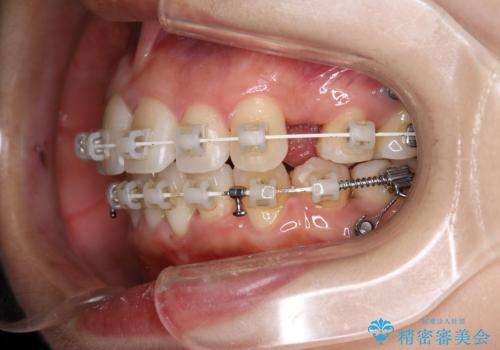

ワイヤー矯正治療中に歯の着色を綺麗に

- ワイヤー矯正治療中にクリーニングを希望されました。

日常的にコーヒーを飲むそうで、装置周りの着色が気になるとのことでした。

エアフロー60分コースを行いました。